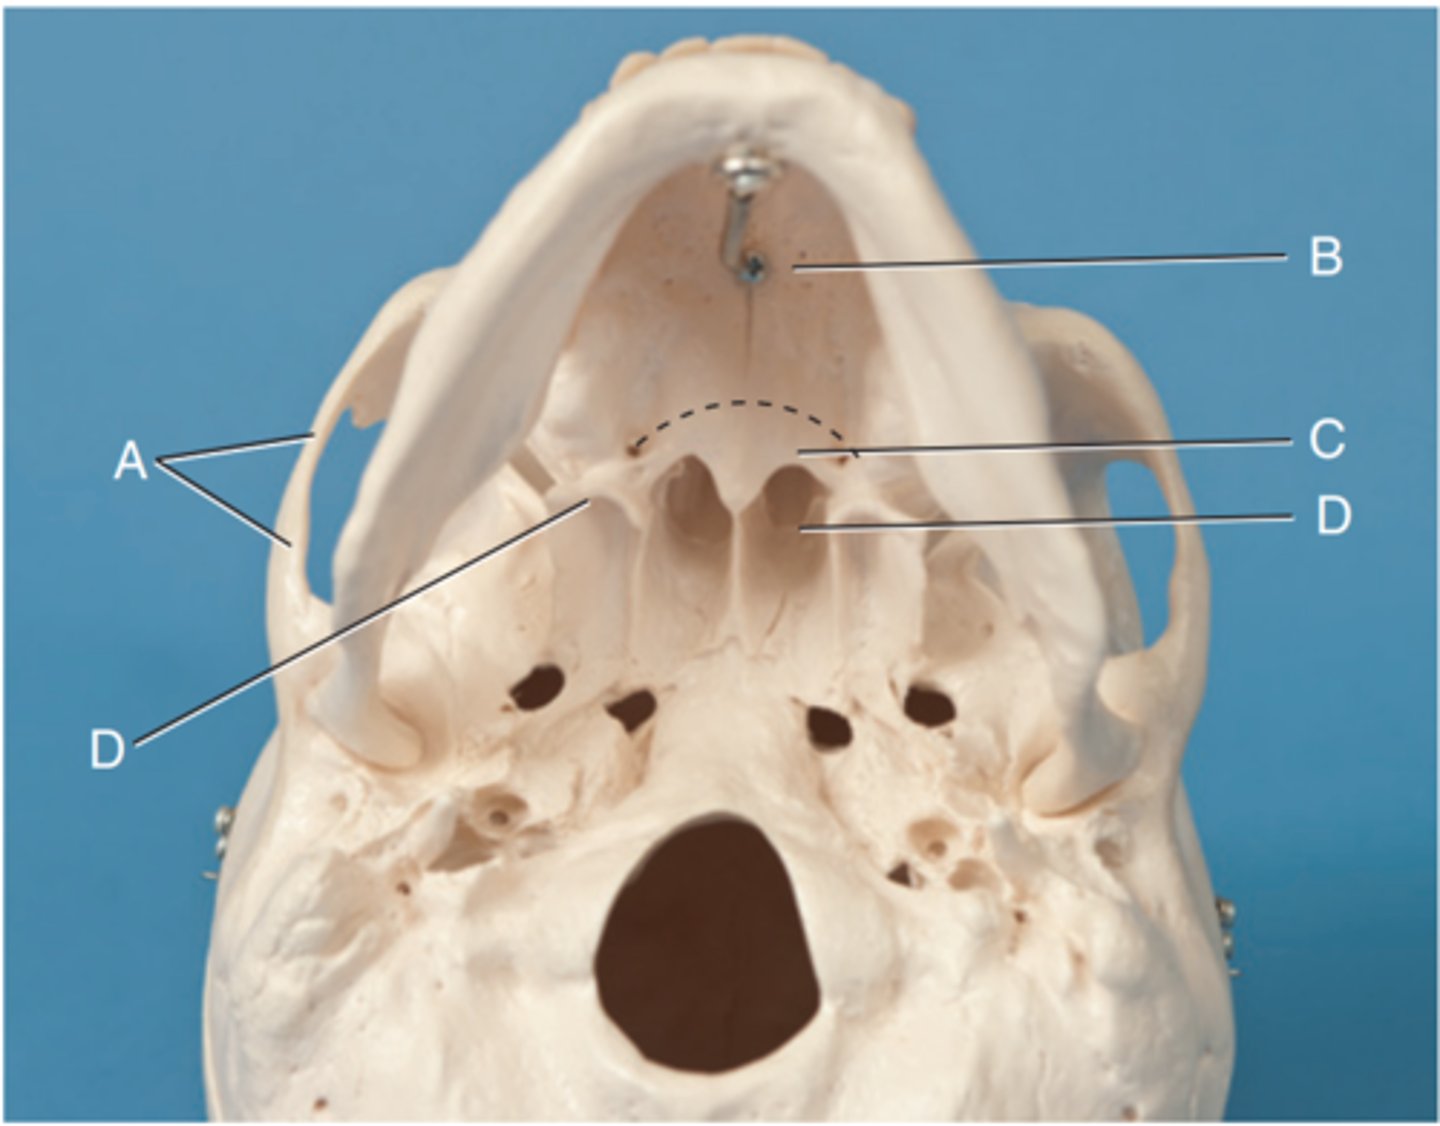

Label A

Posterior clinoid processes

Label B

Petrous ridge or petrous pyramid

Label C

Parietal bone

Label D

Occipital bone

Label E

Foramen magnum

Label F